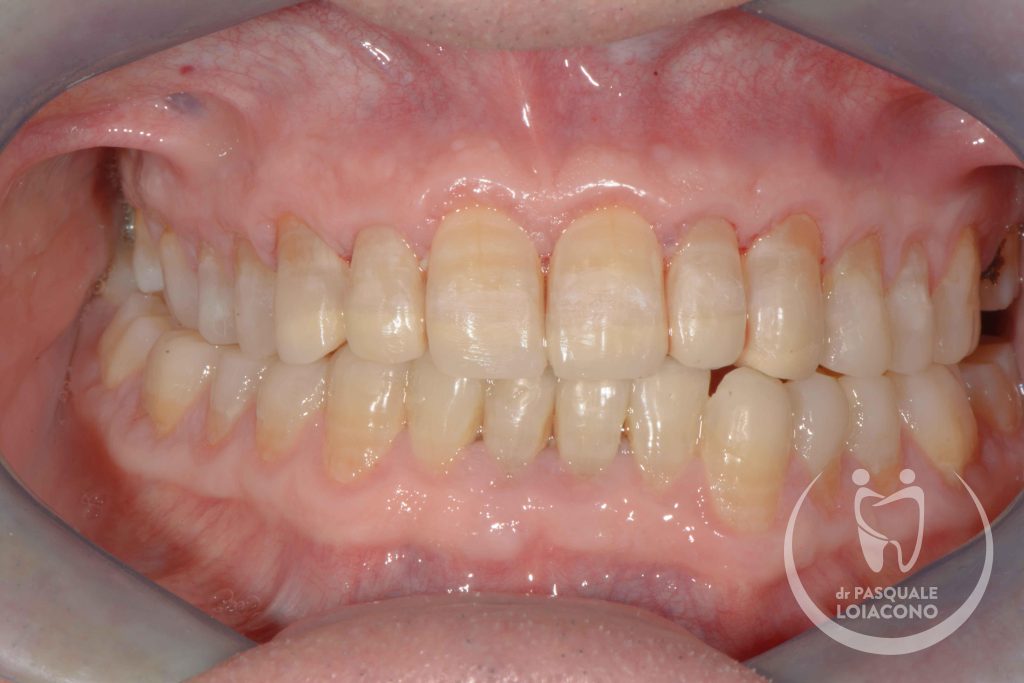

In generale nel funzionamento della bocca è preferibile che ci sia la simmetria tra le parti destra e sinistra, perché segno di equilibrio muscolare. Le asimmetrie delle arcate sono spesso la conseguenza di abitudini di masticazione prevalente su un solo lato, condizione non ottimale perché potrebbe creare tensioni nel nostro sistema posturale e sulle articolazioni della mandibola.

Quando ci sono problemi articolari della mandibola è necessario ricercare un’occlusione dentaria che rimetta il sistema il più possibile in equilibrio. L’organo della masticazione non è costituito solo da denti, ma anche da articolazioni e componenti neuromuscolari, e solo quando tuti i componenti sono in armonia tra loro si può avere salute e benessere. In realtà non tutti gli studiosi sono d’accordo su questioni fondamentali e non esiste visione unanime. Questo vuol dire che potreste incontrare un odontoiatra che sconsiglia qualsiasi trattamento, se non fisioterapia e massaggi o addirittura solo terapia psicologica di sostegno. All’opposto esistono scuole di pensiero che identificano nell’occlusione il fattore scatenante di una patologia che comunque resta complessa e multifattoriale. Da dentista desidero che la bocca funzioni bene e segua le regole stabilite, perché considero comunque positiva questa condizione, e quindi cerco di riportare l’occlusione del paziente verso una condizione il più possibile ideale.

Nello studio del Dr Pasquale Loiacono si esegue diagnosi e terapia dei diversi problemi gnatologici, con terapie personalizzate protesiche, additive non invasive ed ortodontiche.